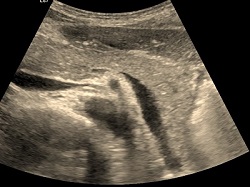

Tętniak Aorty brzusznej.